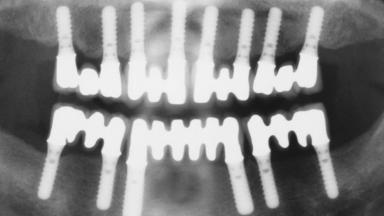

Immediate Loading of Eight Implants in the Maxilla and Six Implants in the Mandible and Final Restoration with Three-Unit and Four-Unit FDPs

# of Implants 14

Type of Implants One-Piece

Defining Characteristics Fully edentulous upper jaw to be rehabilitated with four or more implants

Modality 6+ implants with immediate loading

Bone Volume Horizontally and vertically sufficient

Loading Protocol Immediate

Retention Cemented, with prosthesis margin < 3mm submucosal Cemented, with prosthesis margin < 3mm submucosal

Provisional Implant-Supported Prosthesis Prosthodontic margin < 3 mm apical to mucosal crest Prosthodontic margin < 3 mm apical to mucosal crest